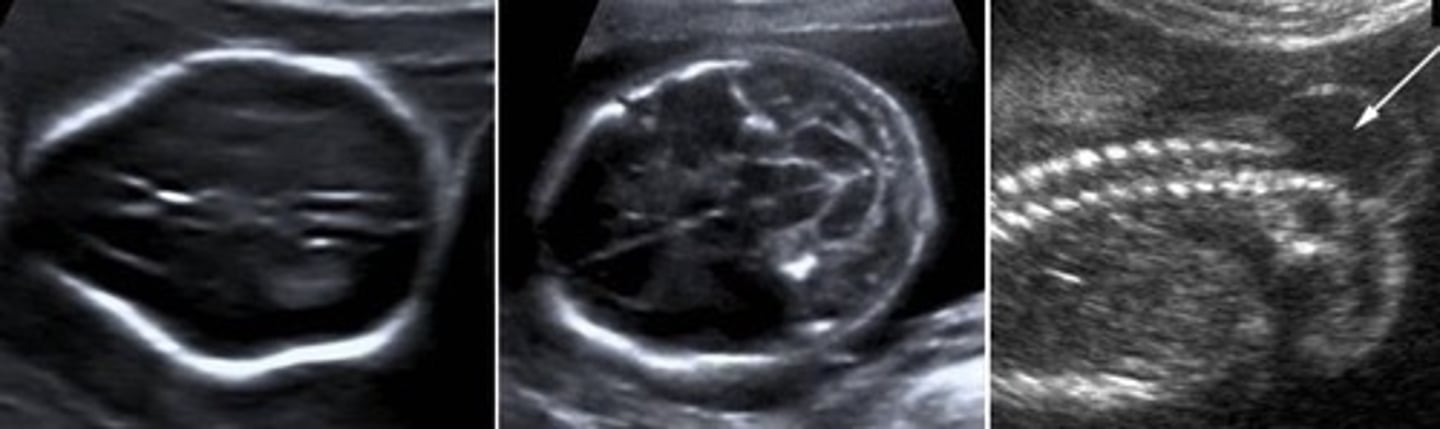

Spina Bifida

Associated with... Lemon-shaped head & Banana-shaped cerebellum

Lemon Sign

Sunken frontal bones

Arnold Chiari

Lemon-shaped head

Banana-shaped cerebellum

No cisterna magna

Mass protruding from spine